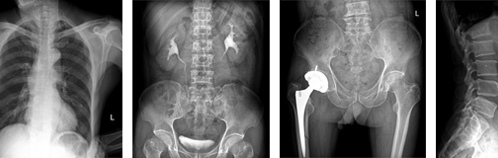

UC臂直接數字化X光機可以垂直、水平運動和轉動,智能化設計,滿足人體所有部位多角度攝影。

4. 探測器可旋轉,能夠滿足人體所有部位(如:下顎、跟骨軸等)多角度攝片要求。

5.17×17英寸成像面積,完全滿足臨床檢查需要。